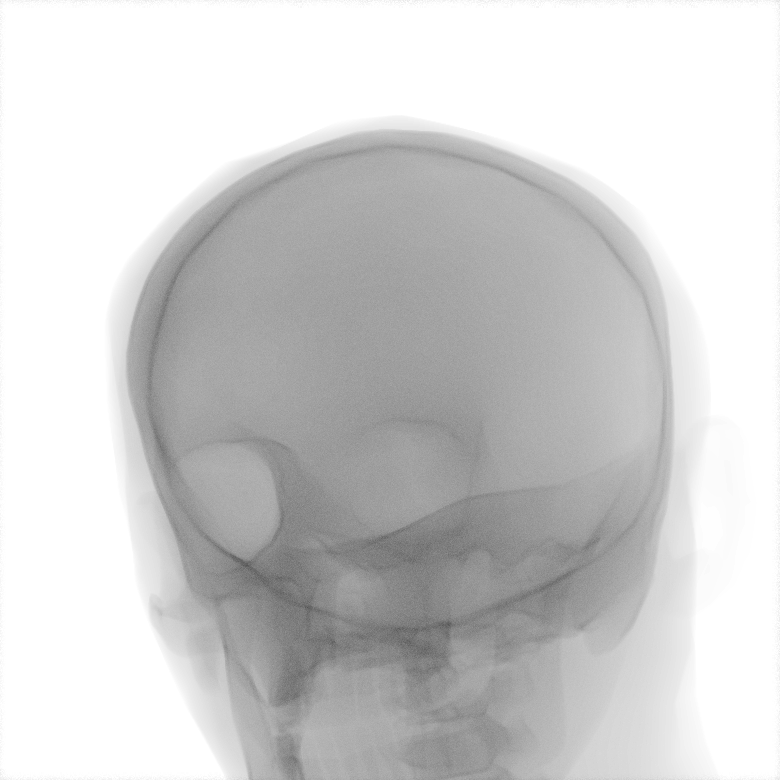

Refer to caption

Figure 2: Dataset overview. The synthetic domain contains Low and High dosage samples generated using the Mentice VIST® simulator; the real domain includes Low, Normal, and Exposure dosage categories acquired from a skull phantom using the Philips Azurion IGT system.

We develop and release a new dataset of real and synthetic head X-ray images, X-DigiSkull, to study the domain adaptation. The dataset consists of synthetic X-ray images of a human skull generated using the Mentice VIST® simulator 111https://www.mentice.com/simulator/vist-g7. Real‑time X‑rays are generated by holding the 3D voxel “patient” head model with per‑voxel attenuation, casting one ray per detector pixel to form a digitally reconstructed radiograph and then approximating scatter, focal‑spot and detector blur, grid/heel effects and detector response, adding quantum/read noise and final image post-processing as the C‑arm and devices move. Real images are acquired from a clinical-grade physical skull phantom using the Philips Azurion Image Guided Therapy (IGT) system. Images are captured from common IGT working positions for neuro procedures. The dataset consists of multiple orientations and is available in three different radiation dose settings: low, normal, and exposure (Philips exclusive), the latter offering enhanced image quality and detail, as shown in Figure 2. This consists of viewing angles rz[40,+40]r_{z}\in[-40^{\circ},+40^{\circ}], ry[40,+40]r_{y}\in[-40^{\circ},+40^{\circ}], rx[40,+40]r_{x}\in[-40^{\circ},+40^{\circ}] with respect to the starting position in 10 increments and up to 3 images at each position to capture the noise present. This results in a total of 2,187 real images. The coordinate systems of the real and synthetic environment are aligned and synthetic images are rendered to approximate the same viewpoints as the real phantom images with the patient table starting at a similar position.The head 3D model used in the simulation is meticulously built from a real clinical case. We capture the synthetic images in finer increments of 5 across the three angles, producing the 5,832 (18318^{3}) images 222Data available at https://zenodo.org/records/16535437. The aim of this alignment is not to achieve precise supervised image translation, but rather to establish a consistent reference structure that preserves spatial features. The composition of the dataset is summarized in Table 1, which contains information on the splits and the number of images available. All images are cropped and resized to 780×\times780 pixels. The test set is obtained by uniformly sampling 15% of viewing angles and corresponding images to ensure a representative distribution. For our experiments, we focus on the task of converting synthetic images at high dose to real images at normal dose.